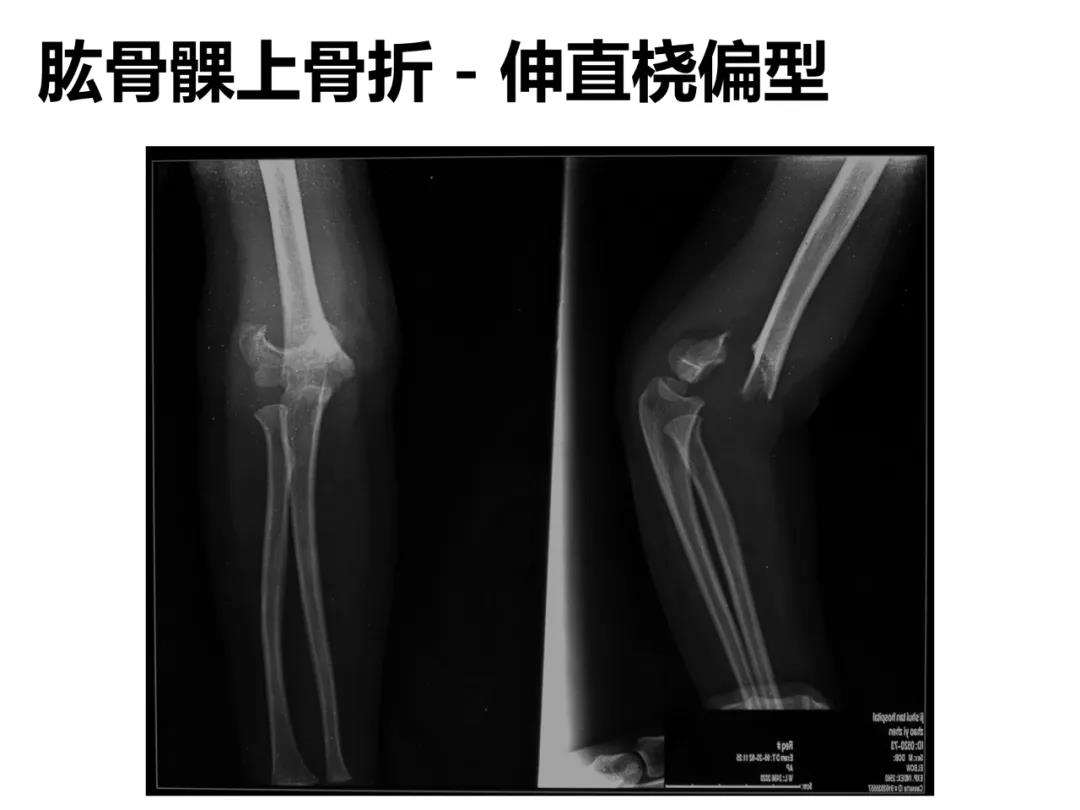

小儿骨科X线片汇总,临床读片宝典!